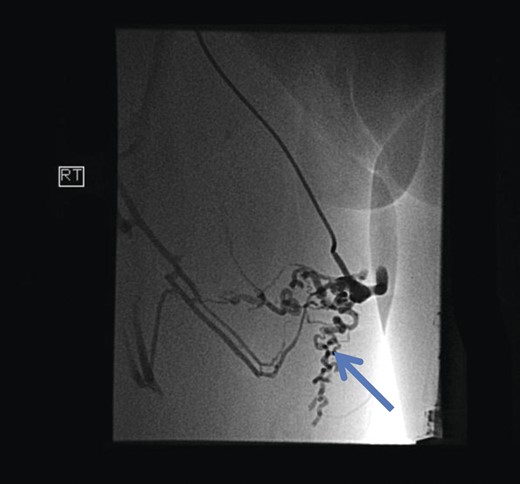

The superficial external pudendal vein was embolized with 1% sodium tetradecyl sulphate and then coiled through a contralateral puncture under fluoroscopic guidance (Figs 3 and 4). The procedure went uneventfully with successful obliteration of the communicating thigh veins to vulval varices (Fig. 5) and the patient was discharged home the same day.

Pre-embolization fluoroscopy showing communication of thigh veins to vulval varices (blue arrow).